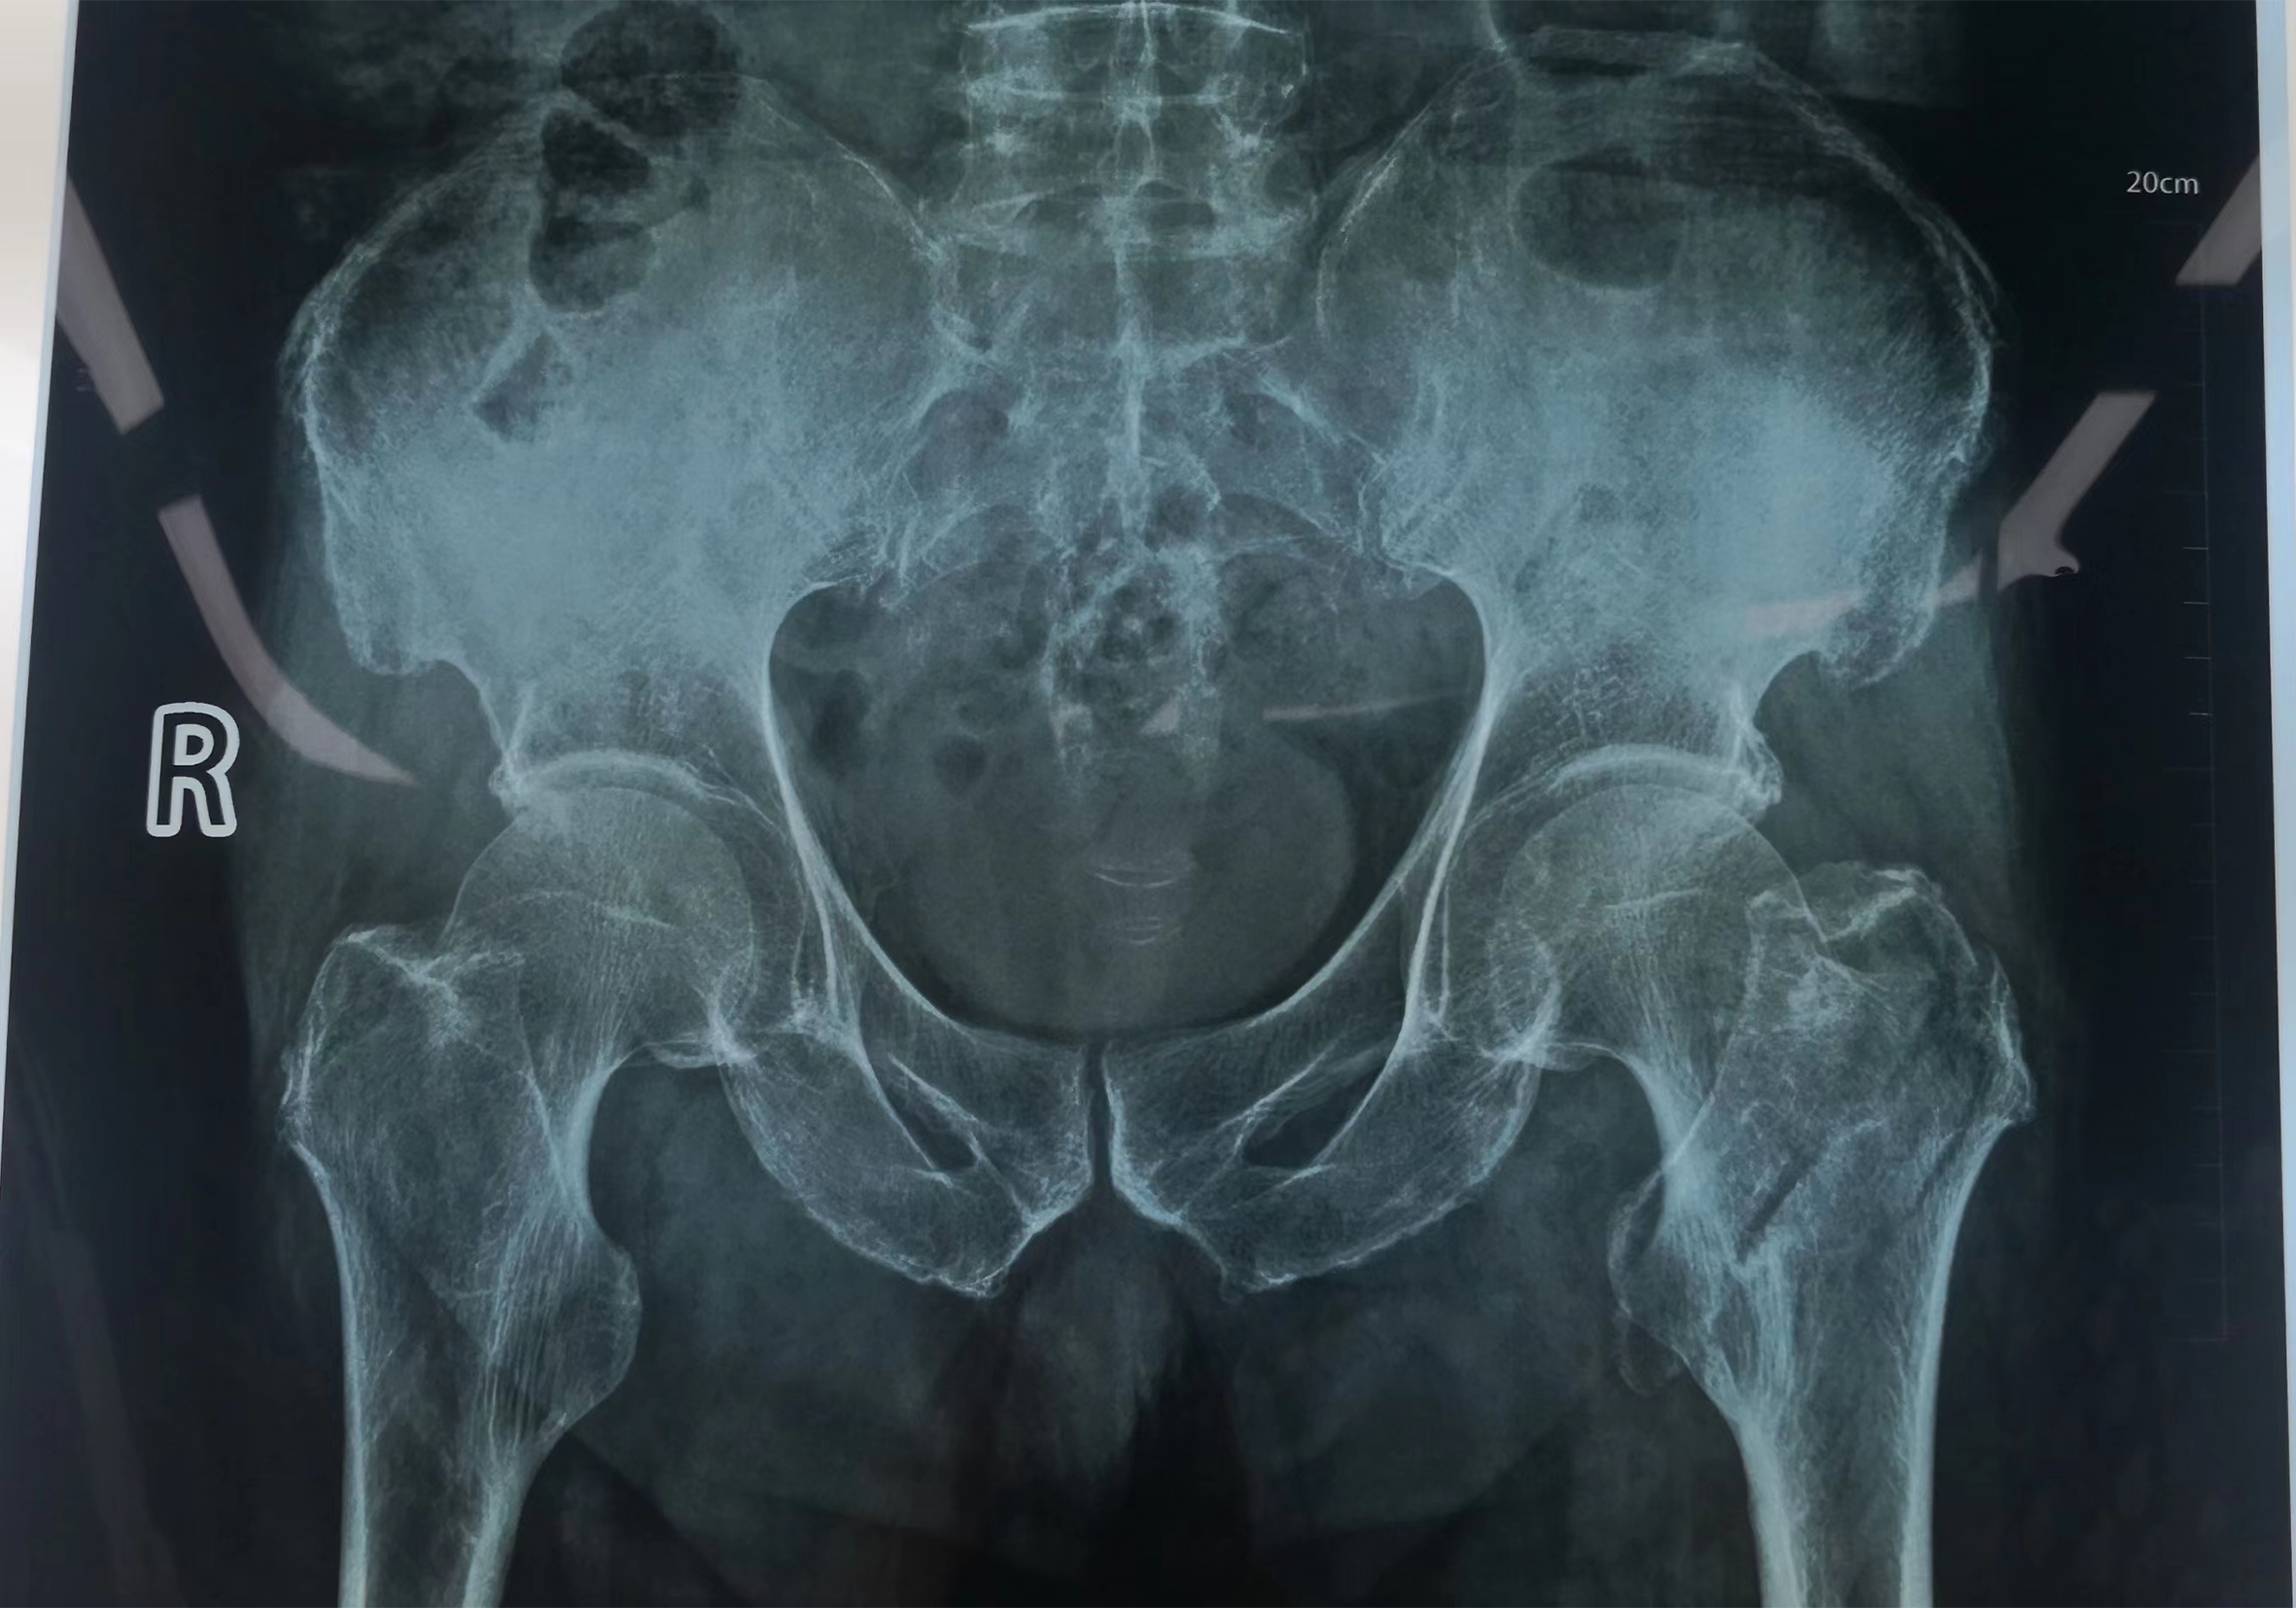

找庞润明主任治疗。诊断为:左股骨粗隆间骨折。 图说:患者术前DR片 入院后给予详细查体,经心电图室、CT室、化验室等各科室的共同配合下,迅速完善各项术前检查。通过庞润明主任及主管医生认真评估,分析了可能遇到的各种困难,决定老人可以行手术治疗。 图说:患者术中DR片 在手术室人员的共同配合下,手术顺利完成,术后髋关节正侧位DR 片,手术非常成功。 图说:患者术后DR片 股骨头置换术后的护理同样非常的重要,护士对大爷及家属进行了健康宣教,帮助患者做了如何坐立、上下床的练习,最终在我们医护人员的共同努力下,患者下地走路了,露出了满意的笑容。 图说:在医护人员的指导下患者下地走路 通过我们全体医护人员的精心照顾,细心的呵护,点点滴滴的付出,给患者鼓足了勇气,更加有信心面对病痛的折磨,战胜了病魔的纠缠。健康所系,性命相托!我们骨科全体医护人员竭诚为您服务!